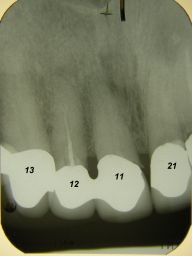

Das etwas dunkle Röntgenbild links(6/2003) zeigt diverse Probleme. Hier interessiert, daß der Zahn 22 (sprich: "zwei", "zwei") am 28.10.05 Schmerzen bereitete, weil der Zahnnerv unter Eiterbildung abgestorben war. Es brauchte 3 medikamentöse Einlagen, bis der Zahn ruhig war und am 18.11.05 eine Wurzelfüllung und einen Titanstift in den Wurzelkanal bekommen konnte. Bei der anschließenden Röntgenkontrolle rechts fiel der schlechte Randschluß der Krone 22 auf.

Weil auch die anderen Schneidezahnkronen (12-22) durch Randreparaturen und den schlechten Randschluß erneuerungsbedürftig aussahen, wurden 4 Einzelkronen geplant. Vorher hieß es aber noch, die schlechte Wurzelfüllung im Zahn 12 (Röntgenbild links) besser zu machen. Hierfür wurden am 17.2.06 die alten Kronen 11 und 12 entfernt. Rechts das Bild nach Entfernung von alten Füllungen und Karies.